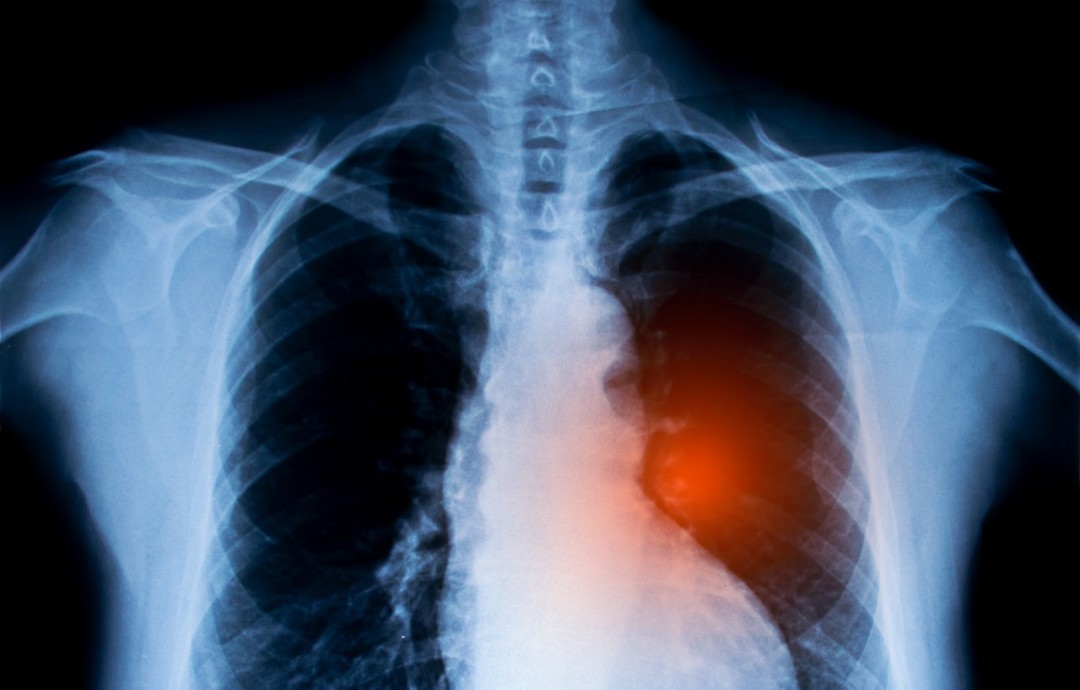

放射性肺炎是肺癌放疗常见的并发症,它是放射野内正常肺组织受损伤引发的炎症反应。其严重程度与放射剂量、肺部照射面积和照射速度紧密相关。

在急性期,肺部呈现渗出性炎症反应;到了慢性期,则会发展为广泛的肺组织纤维化。患者一般在放疗后 2 - 3 周出现症状,常见的有刺激性干咳、气急、心悸、胸痛,可能伴有低热,少数情况会出现高热。随着肺纤维化加重,气急症状会进行性加剧,而且容易合并呼吸道感染,进一步加重病情。

在放疗期间,医护人员会密切观察患者是否出现呼吸道症状以及体温是否升高。一旦通过 X 线检查发现肺炎,需立刻停止放疗,让患者卧床休息。治疗主要以对症为主,若肺部发生继发感染,会使用抗生素;患者出现胸闷气促时,给予氧气吸入;肾上腺糖皮质激素可减轻炎症反应,促进渗出吸收。同时,患者应摄入高热量、高蛋白、易消化的食物,高热患者会接受物理或药物降温。医护人员还会关注患者咳嗽、咳痰及痰液性质,协助拍背咳痰,剧烈咳嗽时会使用止咳药。